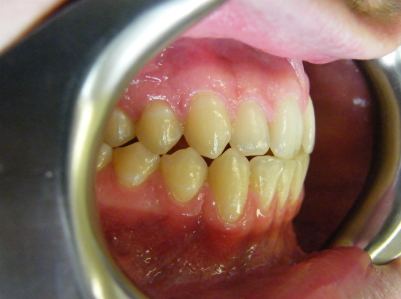

Patient 4: Upper and lower crowding, edge to edge bite and crossbite.